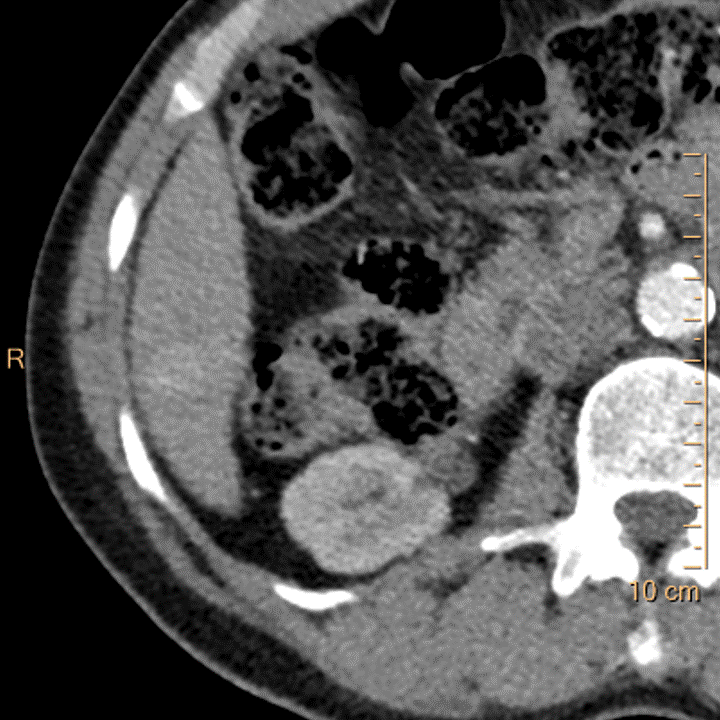

Arterial phase, conventional image. Scan done with 35 mL contrast. See the enhancement?

Arterial phase, 40 keV mono-E image. No comment needed.